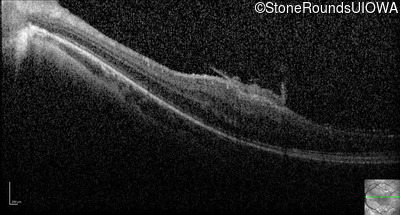

Optical Coherence Tomography - Right - 20/2000

Exemplar / OCT Stack